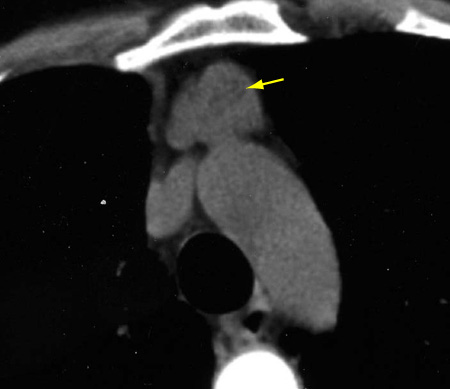

Tomografia computadorizada (TC) do tórax mostrando timoma com encarceramento e invasão da veia inominada esquerda

Do acervo de Cameron Wright, MD; usado com permissão